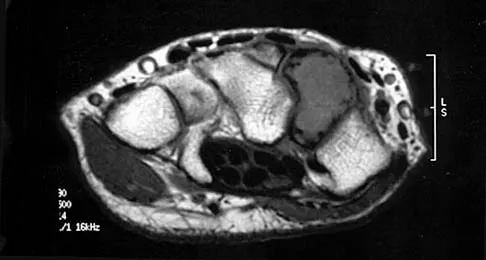

A healthy 16-year-old boy has had increasing pain in the right knee for the past 3 months. Examination reveals warmth and swelling around the distal femur. Radiographs and an MRI scan are shown in Figures 51a through 51c, and a biopsy specimen is shown in Figure 51d. What is the most likely diagnosis?

Explanation